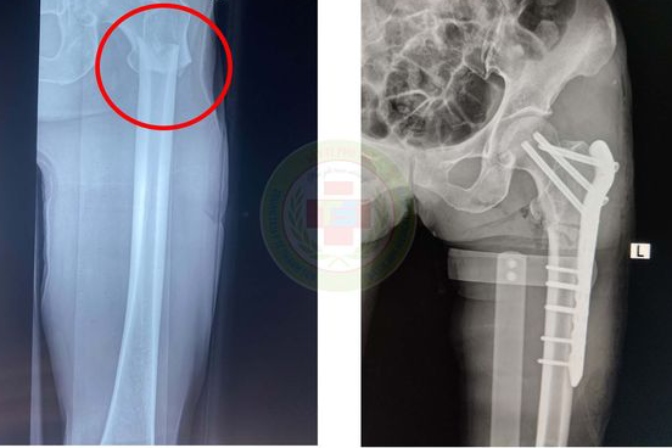

Trong lúc chăn thả gia súc, người phụ nữ đã bị trâu tấn công dẫn tới gãy rời và biến dạng xương đùi bên trái.